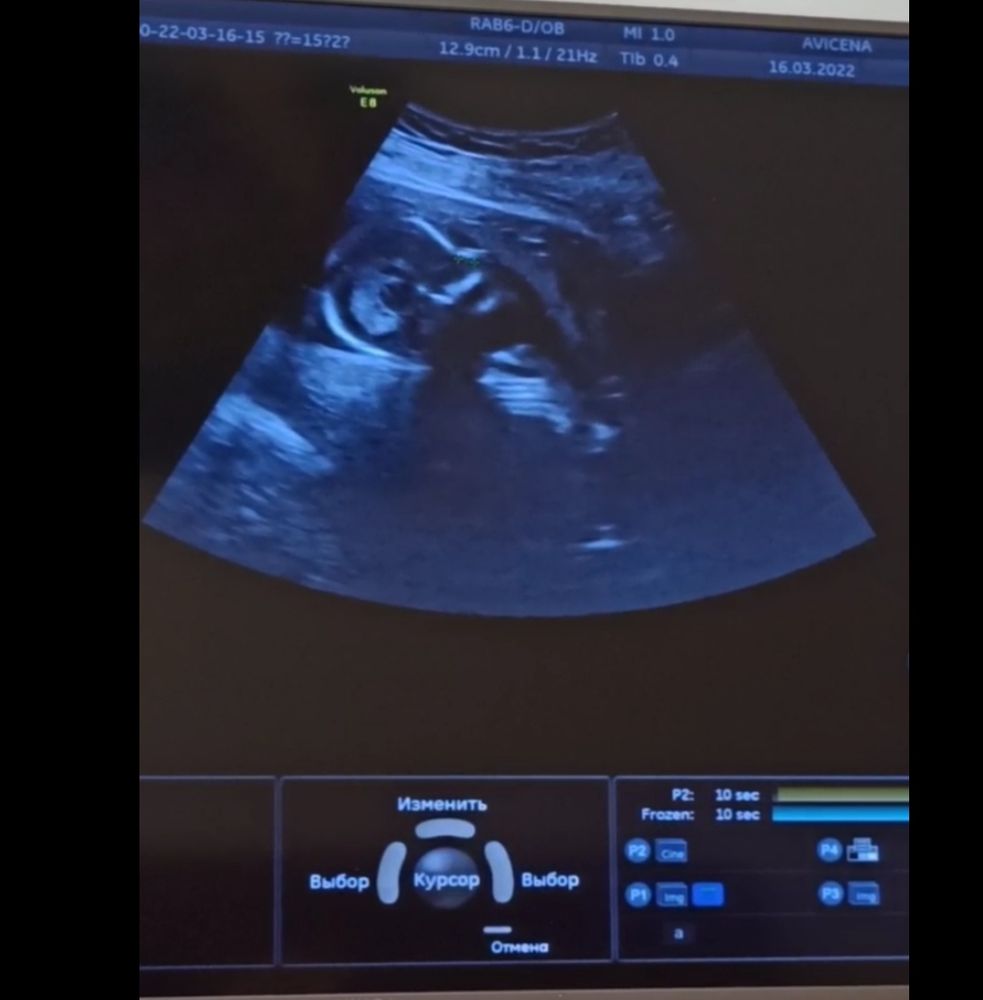

16-ая неделя, наконец-то встретились!

16.03.2022

По профилю на мальчишку похож! Лёгкой вам беременности! Ваша история ещё раз доказывает,что крепкому и здоровому ребенку ничто не может помешать расти и развиваться ;)